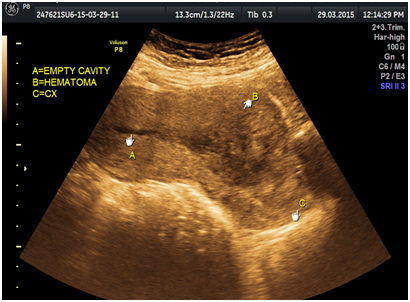

A 29-year-old multiparous woman at 11weeks’ gestation was referred to our hospital for termination of pregnancy due to suspected placenta accreta or cesarean scar ectopic by abnormal vasculature around lower uterine segment gestational sac on ultrasound. She had delivered 2male children by cesarean section. The patient underwent ultrasound due to complain of vaginal bleeding. It revealed lower uterine segment pregnancy with abnormal vasculature in the placenta bed suspicious of placenta accreta or cesarean scar ectopic pregnancy about 10weeks gestation (Figure 1). The decision was done to evacuate the pregnancy vaginally by surgical means. The patient underwent surgical evacuation under ultrasound guidance but severe vaginal bleeding occurred. The procedure was ended and uterovaginal packing was done for 24hrs. The patient was vitally stable. The procedure was performed transabdominal ultrasound examination after 24hrs that revealed bulky uterus with hematoma inside cavity and there was a defect (3cm×2.0cm) in the lower anterior uterine wall with no fluid collection in the abdomen (Figures 2-5). The patient was vitally stable with no vaginal bleeding. We removed the vaginal pack intraoperative under general anesthesia, prepared for laparotomy in case of severe bleeding. No bleeding occurred, the patient discharged after 1 week and follow-up after one month revealed normal uterus.

Figure 1 lower uterine segment with abnormal vasculature in placenta bed suspicious of early placenta accreta or cesarean scar ectopic pregnancy.